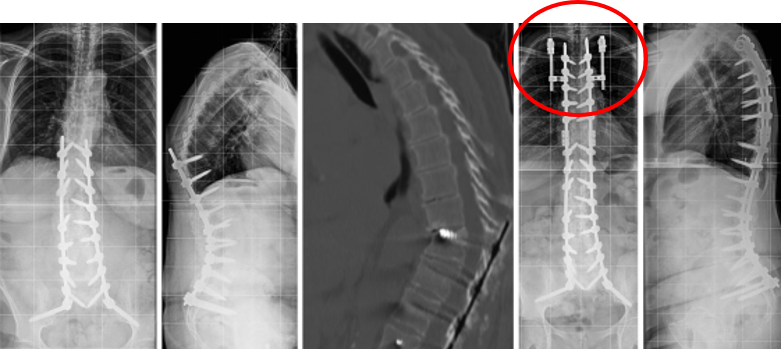

(2)骨水泥强化(UIV和UIV+1)

图30 相关文献报道,对UIV和/或上方邻近椎行骨水泥强化,可降低PJK的发生率; UIV和UIV+1强化有更显著效果

图31 左:骨水泥强化;右:尸体标本的生物力学分析

(3)肋骨固定

T10骨盆固定,出现交界性后凸

行翻修手术:T9/10SP截骨,延长到T4固定,预防性双侧肋骨固定(VEPTR)

图32-33 肋骨固定